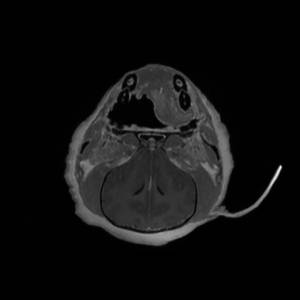

Main Gallery

Playing with a photo gallery function. It is possible to have multiple galleries, each within a namespace.